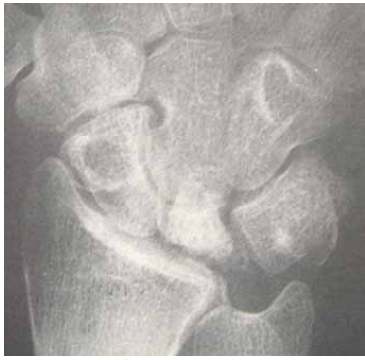

40 一位 32 歲果園工作婦女來門診主訴右腕疼痛已有近半年,理學檢查發現右腕背屈活動有明顯拘限, X 光檢查如圖所示,最可能的診斷是:

(A)正中腕隧症候群(carpal tunnel syndrome) (B)舟狀骨骨折不癒合(scaphoid fracture non-union) (C)半月狀骨缺血性壞死(Kienböck disease) (D) de Quervain’s tenosynovitis